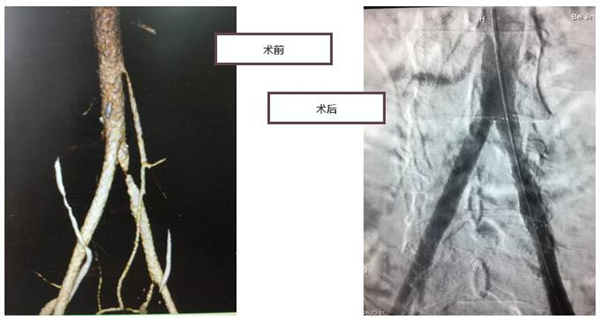

为查出病因,一周后,何医生又为郭大哥进行了腰腹部加强CT的检查,发现郭大哥左腹下端总动脉重度狭窄,确诊为左侧髂总动脉闭塞症。

得知病因,郭大哥非常惊讶,原来血管栓塞不仅会发生在心脏和大脑,还可能发生在肢体部位。明确诊断之后,由普外科何永健医生主刀,为郭大哥进行了左髂总动脉球囊扩张和支架置入手术。通过如针细的微导丝,深入血管内部,扩张支撑狭窄血管,恢复下肢动脉的正常血供。仅30分钟,郭大哥的左股动脉和腘动脉搏动清晰,自觉肢体明显发热。术后次日便能下地正常行走。